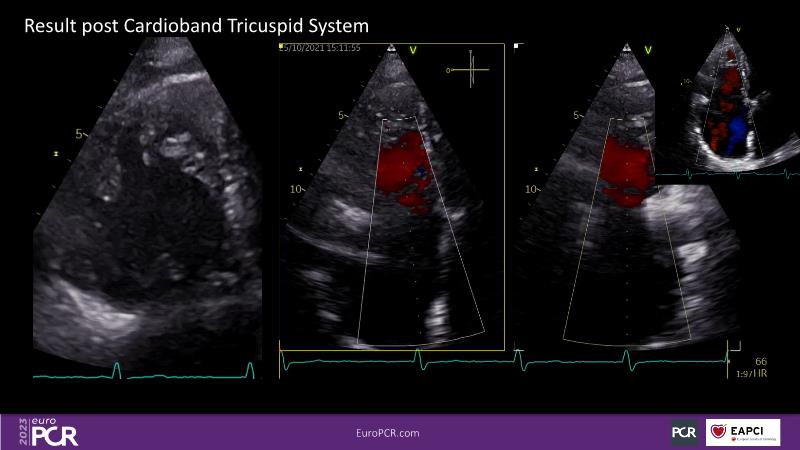

Tailoring tricuspid regurgitation patient treatment with the PASCAL Precision system

Watch this session to discuss exciting cases of tricuspid regurgitation, learn about the proposed new integrated classification for tricuspid regurgitation and enjoy a live presentation of the PASCAL Precision Repair System using a beating heart simulator, among others!

- To discuss the different tricuspid regurgitation phenotypes that can be treated with the PASCAL Precision repair system

- To participate in a case-based discussion using the PASCAL Precision repair system for the treatment of tricuspid regurgitation